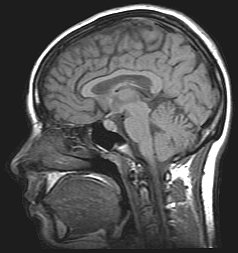

Om het resultaat te visualiseren wordt de scan door de computer meestal als een aantal 'plakjes' van het lichaam of het hoofd gepresenteerd, die naar keuze in de drie anatomische vlakken (sagittaal, transversaal, coronaal) kunnen worden bekeken. Vaak kan zelfs elk mogelijk vlak onder willekeurige hoek gekozen worden - de gegevens kunnen door een snelle computer op iedere gewenste manier worden gepresenteerd, de enige beperkende factor is de benodigde rekentijd. Ook driedimensionale weergaven van bepaalde structuren in een bepaalde lichtval behoren tot de mogelijkheden, zolang er maar een manier bestaat om met behulp van de software te onderscheiden welke voxel (beeldpunt) tot de structuur behoort en welke niet. De software-ontwikkeling is daarom onverbrekelijk verbonden met die van de andere technieken.

Met moderne MRI-scanners is het scheidend vermogen ongeveer 0,3 millimeter (2005).

Neurologie

Röntgenstraling wordt geabsorbeerd door materialen. Ze kan dus onderscheid maken tussen bijvoorbeeld bot (bevat calcium) en lucht in de longen. MRI kan onderscheid maken tussen weke delen en is daardoor effectiever bij de meeste aandoeningen, maar niet bij botafwijkingen; voor een schedelbasisfractuur zal men een CT-scan met röntgenstraling maken, voor een hersenkneuzing een MRI.